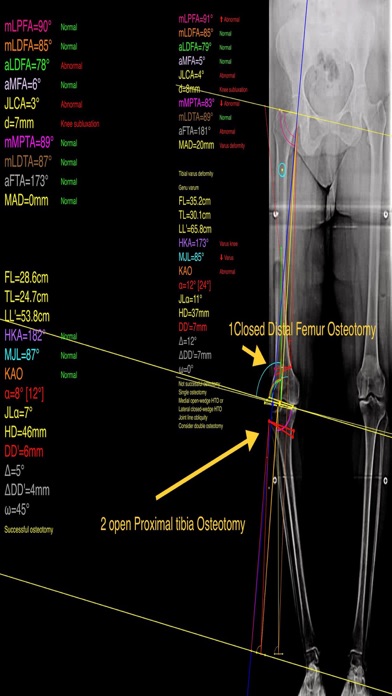

Mal alignment of the hip, knee, and ankle leads to premature cartilage damage and to development of degenerative arthritis of knee joint. Femoral and tibial osteotomies around the knee are established procedures for the restoration of the physiological load distribution of pressure at the knee joint. Accurate preoperative planning is mandatory to avoid under correction or overcorrection of axes or placing the joint-line in obliquity that ends to insufficient postoperative alignment.The majority of osteotomies are still planned and performed using conventional techniques drawing over transparent papers, cumbersome measurements etc.

-the amount of correction preoperatively by calculating the dimension of  wedge size , the correction angle and osteotomy gap opening or closing.

-mechanical axis deviation (in mm) MAD, anatomical and mechanical femoral axes angle (aMFA),mechanical lateral proximal femoral angle (mLPFA), mechanical lateral distal femoral angle(mLDFA), joint line convergence angle (JLCA),mechanical medial proximal tibial angle (mMPTA), Mechanical lateral distal tibial angle (mLDTA), Hip Knee Ankle line (HKA) ,Mid joint line (MJL) orientation.

-objectively the deviation or deformity in the frontal plane (varus or valgus) and differentiate the level of deformity (femoral and or tibial origin) and according to measured angles objectively suggest where indicated, medial or lateral, open or closed-wedge distal femur osteotomy or high-tibial osteotomy or double osteotomies  and avoiding unwanted obliquity of the joint line

-pressing + or - button, one degree of correction is added or subtracted respectively and the second plane of osteotomy emerges and printed in screen real offering real time simulation of the wedge osteotomy in an instant to comprehend in real time what parameters are affected and modify favourably the correction angle. All above mentioned angles and all limp axes are redrawn and updated accordingly for the given new correction angle. The drawn schematic gives the impression of settings  act as a whole interchangable interacting unit.